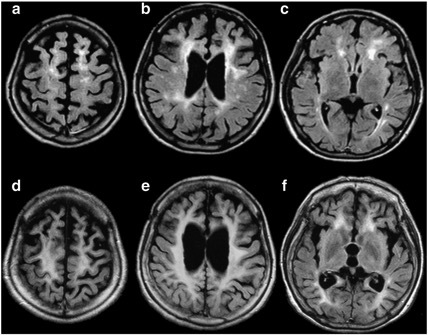

案例 11:51 岁女性,诊断为 HDLS。

图 12 a~c:患者起病时的 MRI 提示深部白质多发小片状 FLAIR 高信号病灶;d~f:5 年后复查,可见病灶融合,表现为 FLAIR 上脑白质广泛的高信号